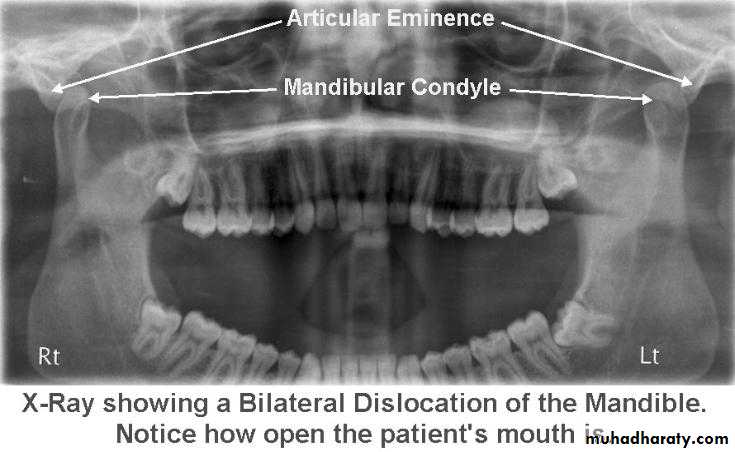

8Radiology

Radiography confirms a clinical diagnosis.The condyle may translate beyond the articular eminence normally, without a dislocation, so clinical information is essential. The condyle will be anterior and superior to the ‘summit’ of the articular eminence.

Dislocation

NB. Normally: the condyle may be translated anterior to the eminence as far as 5 mm.Dr. Mohammed Amjed Alsaegh, 2021